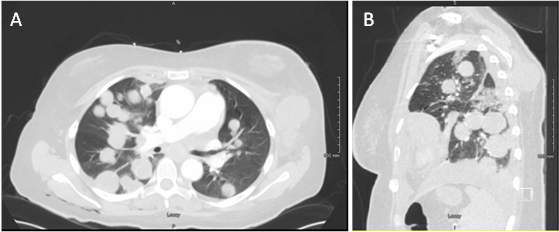

Light microscopy of biopsied tissue showed patternless sheeting of neoplastic cells with cytoplasm containing eosinophilic inclusions and peripherally located large round-to-oval nuclei. (Figure 2) Immunohistochemically, neoplastic cells were focally positive for S100, Sox10, myoD1, and desmin as well as diffusely positive for vimentin. Lesional cells were negative for HMB-45, Melan-A, CD31, CD34, ERG, smooth muscle actin, myogenin, caldesmon, keratin 7, keratin 20, Oscar keratin, and keratin AE1 AE3. Non-contrast computed tomography scan of the chest, abdomen, and pelvis revealed numerous bilateral cannonball lung tumors, extensive bilateral axillary and mediastinal adenopathy, and a soft tissue mass involving the left upper back superior to the site of the surgical debridement. (Figure 3) These findings were consistent with a diagnosis of dedifferentiated primary melanoma with rhabdoid and heterologous rhabdomyoblastic features.

Figure 3 A) CT scan of the chest, abdomen, and pelvis revealed numerous bilateral cannonball lung tumors, extensive bilateral axillary and mediastinal adenopathy, and B) a soft-tissue mass involving the left upper back superior to the site of surgical debridement.